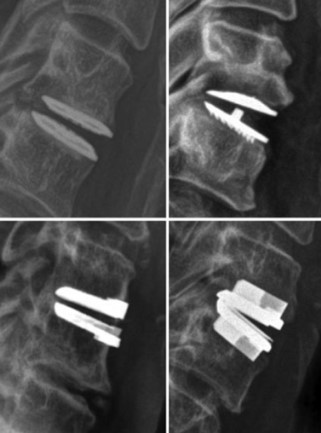

Study Overview Cervical total disc replacement (CTDR) involves removal of the damaged cervical disc and replacement with an artificial device that is designed to maintain normal neck movement and relieve symptoms. While CTDR can help many patients, some patients experience problems over time such as recurring pain or discomfort in their neck and/or arms. Other […]

Study Overview Cervical total disc replacement (CTDR) involves removal of the damaged cervical disc and replacement with an artificial device that is designed to maintain normal neck movement and relieve symptoms. While CTDR can help many…